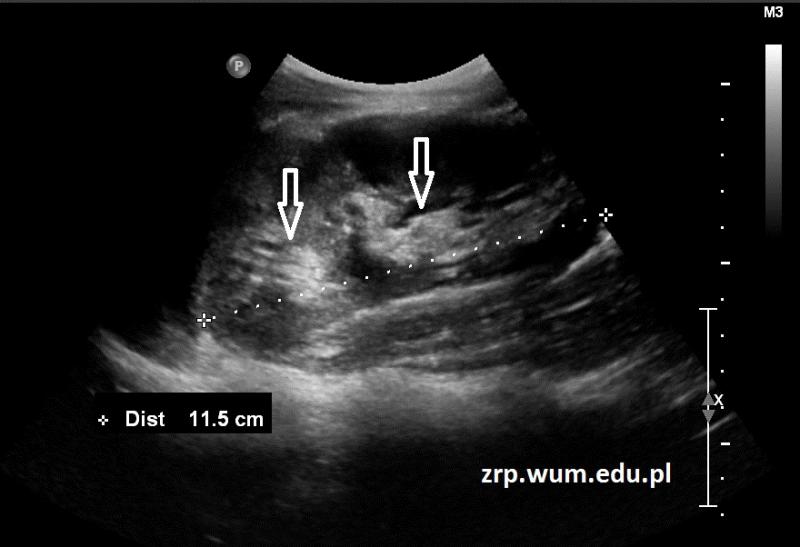

Przypadek 15: 16-latek ze stwierdzonymi w badaniu usg cechami zdwojenia układu kielichowo-miedniczkowego nerki lewej.

Rozpoznanie: W badaniu usg stwierdzono w nerce lewej dwa echa centralne (strzałki) z widocznym między nimi miąższem nerkowym. Bez poszerzenia UKM.